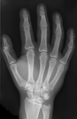

మానవుని చేతిలో మణికట్టు, అరచేయి మరియు వేళ్ళు చేతిలోని ప్రధానమైన భాగాలు. మన రెండు చేతులు ఎముకలు, కీళ్ళు, కండరాలు, నాడులు, రక్తనాళాలు మొదలైన వాటితో చేయబడినవి.మానవుని చేతిలో 27 ఎముకలు, వాటిలో వేళ్లకు 14 ఫలాంజిస్ (దగ్గరి, మధ్యస్థ మరియు దూరపు) ఎముకలు వుంటాయి. మెటాకార్పల్ ఎముకలు వేళ్లని మణికట్టుకి కలుపుతుంది. ఇవి ఐదు.

మానవుని చేతిలో 27 ఎముకలు ఉంటాయి:[2] వీనిలో 8 చిన్న కార్పల్ ఎముకలురెండు వరుసలలో అమర్చబడి వుంటాయి. వెనుక వరుసలో నాలుగుముంజేతి ఎముకలతో బంధించబడితాయి. ముందు వరుసలో నాలుగు 5 మెటాకార్పల్ ఎముకలతో సంధించబడతాయి. అయిదు చేతివేళ్లకు కలిపి 14 పొట్టి ఎముకలు (ఒక్కొక్క వేలికి మూడు చొప్పున; కానీ బొటనవేలికి రెండు మాత్రం) ఉంటాయి.

ఇవికాక చేతిలో చాలా సెసమాయిడ్ ఎముకలు ఉంటాయి. ఇవి చిన్న ఎముక భాగాలుగా టెండాన్లలో ఉంటాయి. వీటి సంఖ్య మారుతూవుంటాయి:[3] చాలా మందిలో ఒక జత సెసమాయిడ్ ఎముకలు బొటనవేలి కీలు ప్రక్కన ఉంటాయి.